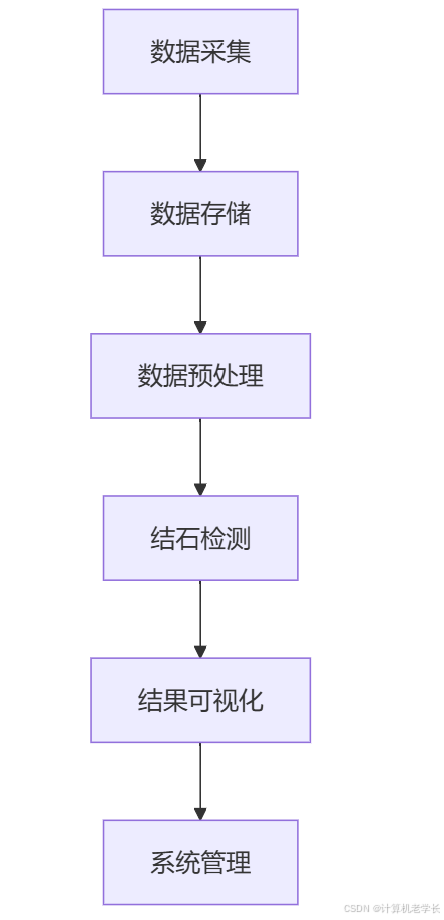

3.1 系统架构

3.2 模块设计

数据采集

数据预处理

结石检测

结果可视化

系统管理